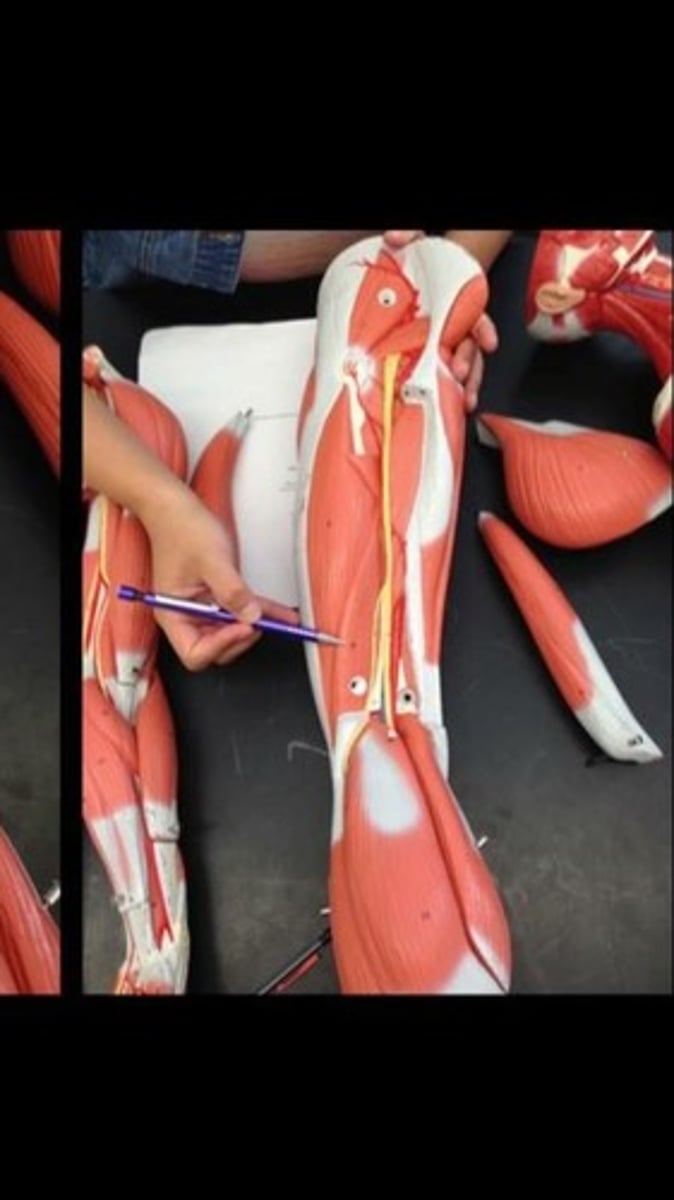

Skeletal muscle terms and structure

114 Terms